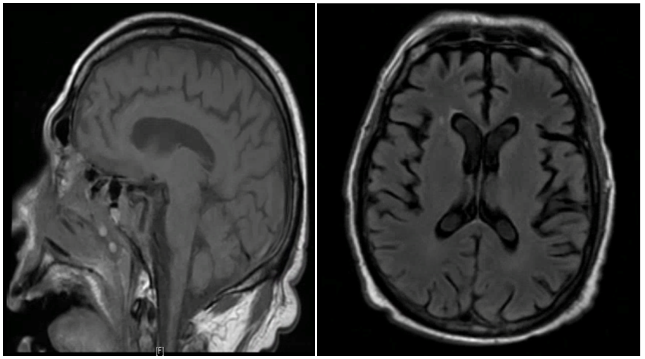

Laboratory work up revealed normal complete blood count, serum electrolytes, kidney function and liver function, his thyroid stimulating hormone was elevated to 77.4 and free thyroxine levels was very low, 0.8. Cerebrospinal fluid analysis was normal, no evidence of infection was found in blood, urine and cerebrospinal fluid and patient did not have fever or any other signs of infection. MRI brain was unremarkable (Figure 1).

Magnetic resonance imaging of the brain is usually normal but may show signs of vasculitis or cerebral atrophy. Our patient had normal neuroimaging (Figure 1-3). EEG may show various degrees of slowing and/or triphasic waves.10 Focal slowing, focal epileptiform discharges, periodic lateralized epileptiform discharges have been seen in isolated cases.7,11,12 Our patient had severely abnormal electroencephalogram with diffuse polymorphic slowing and sharp wave activity suggesting epileptic encephalopathy.

Figure 1 MRI brain on admission.